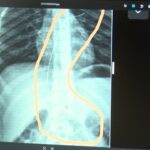

Şırnak’ta yaşayan Semra (37) ve Mehmet Ötün (40) çiftinin oğulları Aram Devran Ötün, mayıs ayında piknikteyken salatalık parçası yuttuktan sonra öksürük ve kusma şikayetleri görülünce Şırnak Devlet Hastanesi’ne götürüldü. Burada çekilen röntgen ve MR’da Aram’ın vücudunda kateter unutulduğu görüldü. Diyarbakır’daki Gazi Yaşargil Eğitim ve Araştırma Hastanesi Kadın Doğum ve Çocuk Ek Binası’na sevk edilen Aram, 5,5 saat süren riskli bir ameliyata alınarak 18 santimetre uzunluğundaki kateter çıkarıldı. Ameliyat sonrası yapılan incelemelerde kateterin kalp kapakçığına ve ciğerlerine zarar verdiği belirlendi.

Ailenin avukatı Ahmet Yalçın, hastane hakkında hem şikayetçi olduklarını hem de dava açtıklarını belirterek, “Müvekkilim Aram Devran Ötün, 2022 Eylül ayında Dicle Üniversitesi Hastanesi’nde Stevens- Johnson hastalığı nedeniyle tedavi gördü. Tedavi sırasında kendisine kateter takıldı. 18 santimetre uzunluğundadır. Bunu takarken büyük bir ihmalkarlık yapılarak vücudunda unutuldu. Mayıs ayında müvekkilim çok öksürdüğü için Şırnak Devlet Hastanesi’ne kaldırıldı. Burada yapılan tetkiklerde kateterin unutulduğu tespit edildi. Daha sonra Diyarbakır Gazi Yaşargil Kadın ve Çocuk Hastalıkları Hastanesi’ne götürüldü. Çok riskli bir ameliyata alındı ve kateter çıkarıldı. Bu kateterin vücutta yol aldığı tespit edildi. İlk giriş yeri ve çıkarıldığı yer arasında çok fark var ve kalp kapakçığı ile ciğerlerine zarar verdiği tespit edildi. Müvekkillerimin hem maddi hem de manevi zararlarını karşılamak adına Dicle Üniversitesi’ne biz başvuruda bulunduk. 30 günlük cevap süresi içerisinde bize geri dönüş yapılmadı. Biz de maddi ve manevi zararların tazminat için Diyarbakır İdare Mahkemesi’ne davamızı açtık ve sorumlulardan şikayetçi olduk” dedi.

Oğlunun piknikte salatalık parçası yuttuktan sonra sürekli öksürmeye ve kusmaya başladığını söyleyen Semra Ötün, “Çocuğum 3 yıl önce Steven Johnson sendromu hastalığına yakalandı. Milyonda bir görülen antibiyotikten kaynaklı bir hastalık. Doktorlar öyle söyledi. Bizi acilen Diyarbakır Dicle Üniversitesi Çocuk Hastanesi bölümüne sevk ettiler. 1 ay yoğun bakım sürecimiz oldu. 28 gün yoğun bakımda, 3 günde serviste kaldı. Damar yolundan, kasıktan serum taktılar. Kateter denilen tel çocuğun vücudunda bırakılıyor. Biz taburcu olduğumuzda fark edilmiyor. 3 yılın sonunda biz bunu fark ettik. Pikniğe gittik. Oğlum salatalık parçası yuttu ve salatalık parçasından sonra akşama kadar öksürdü. Hiçbir şekilde durmadı. Kusuyordu. Ben şüphelenmeye başladım. Çocuğum normal değildi. Sonra eşime danıştım. Akşam 21.00 civarında acile götürdük. Röntgeni ve MR’ı çekildi. Tuhaf bir şey olduğunu anladık. Doktor röntgeni gösterdi. Tel kalmıştı. Çok kötü bir şekilde. Acil doktoru film çektikten sonra bize bir tel parçasını gösterdi. Bizi bekletmeden Diyarbakır’a sevkimizi verdiler. Diyarbakır Gazi Yaşargil Eğitim ve Araştırma Hastanesi Kadın Doğum ve Çocuk Ek Binası’na gittik. Çocuğun kasıklarından anjiyo yolu ile teli çıkaracaklarını ama riskli bir ameliyat olduğunu söylediler. O süreçte çocuk gerçekten sürekli yoruluyordu. İkide bir oturuyordu. ‘Anne çok yoruldum, karnım ağrıyor’ diyordu. Ben ağrı kesiciler ile geçiştirmeye çalışıyordum. Bu telin 3 yıl boyunca çocuğumda kaldığını öğrendim. Ailece yıkıldık” diye konuştu.